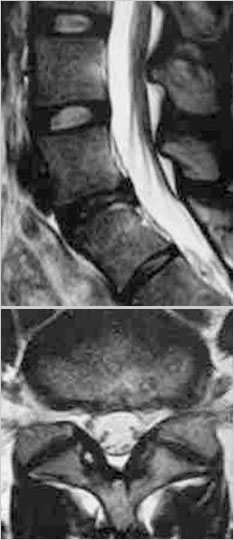

治疗前MRI

治疗后MRI